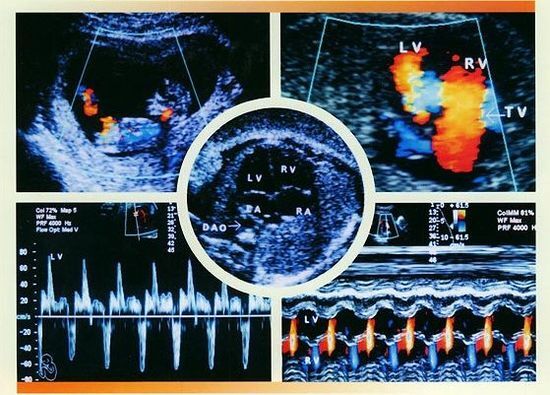

在线咨询先天性心脏病是一种常见的先天性发育畸形。据统计,先天性心脏病的发生率为8‰~1%,我国每年有15万到22万例先心病患儿出生,先心病是常见的主要器官畸形之一,也是导致流产、胎儿宫内死亡以及婴儿死亡的主要原因,那么,做胎儿心脏彩超需要注意什么呢?

二、做胎儿心脏彩超注意时间:准妈妈做胎儿心脏彩超较佳时间在孕周24-28周。因为胎儿24周左右大脑正在发育时期,这时期的胎儿结构已形成,在宫内的活动空间比较的大,胎儿骨骼回声影响比较小,图像比较清晰,这个时候做胎儿心脏彩超彩超可以达到较佳效果。

2、先进产检设备:贵阳和谐阳光医院引进的胎儿心脏彩超,对孕妇产前检查、各种先天性疾病的诊断,是目前上较为先进、科学的超声诊断仪器。